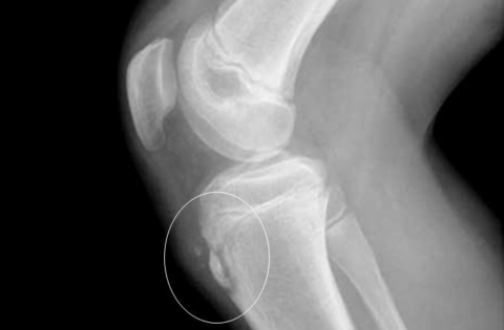

- Рентгенографическое исследование коленных суставов в боковых проекциях; часто наблюдаются характерные «хоботки» в области бугристости большеберцовых костей, нередко вводящие врачей в заблуждение; изолированные костные фрагменты небольших размеров, иногда в количестве 1-2-3. Картина представляется очень разнообразной, напоминающей дробления, искривления и надломы эпифизарного отростка.

Рентгенография коленного сустава при болезни Осгуда-Шлаттера

При прогрессировании патологии рентгенологическая картина меняется в худшую сторону. На снимках наблюдается сдвиг ядра окостенения на 2-5 мм вверх и вперед по отношению к стандартному расположению бугристости или его фрагментация. В некоторых случаях может отмечаться неровность естественных контуров и нечеткость структуры ядра окостенения, а также признаки постепенного рассасывания его частей, однако чаще всего происходит его срастание с основным телом кости с формированием костного конгломерата в форме шиповидного выступа. Такая характерная для болезни Шлаттера «шишка» на поздних этапах заболевания особенно хорошо видна на боковой рентгенограмме и явно прощупывается при пальпации в районе бугристости.

На снимке чётко видны различные виды патологических изменений бугристости